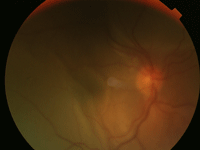

La fase uveítica aguda dura de 2 a 6 semanas y se caracteriza por DR bilateral (Figuras 1, 2 y 3).

Figura 1. Imagen DR seroso en el V-K-H.